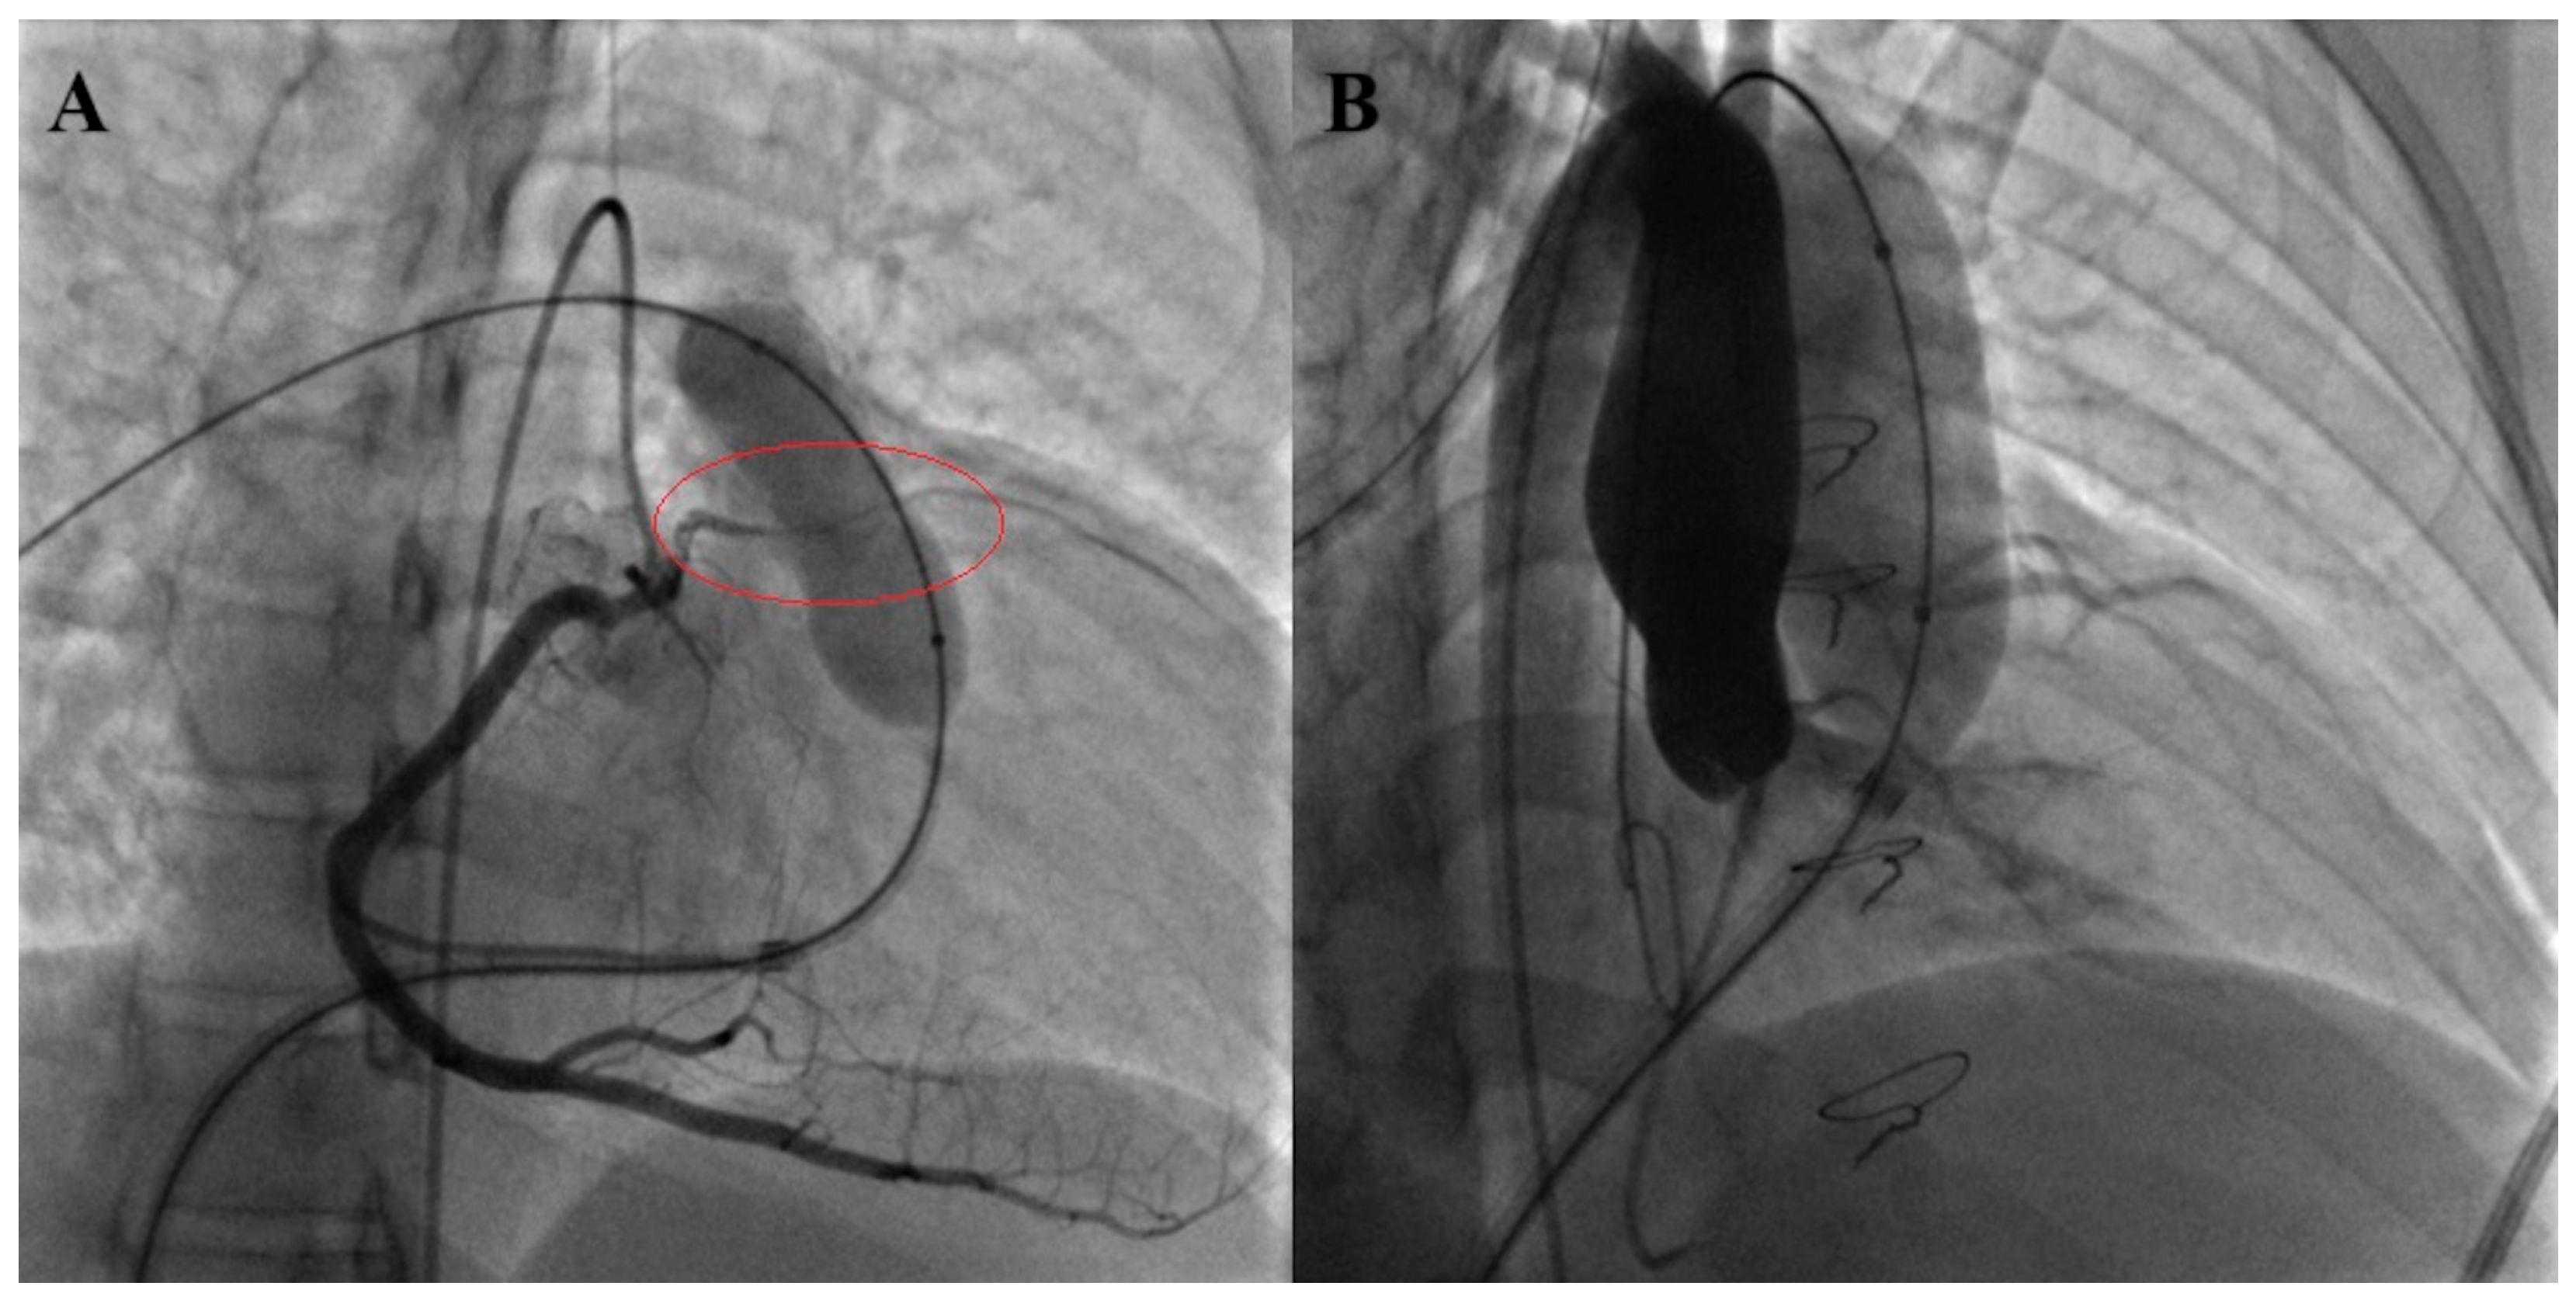

- Fraisse, A.; Assaidi, A.; Mauri, L.; Malekzadeh-Milani, S.; Thambo, J.B.; Bonnet, D.; Iserin, L.; Mancini, J.; Boudjemline, Y. Coronary artery compression during intention to treat right ventricle outflow with percutaneous pulmonary valve implantation: Incidence, diagnosis, and out-come. Catheter. Cardiovasc. Interv. 2014, 83, E260–E268. [Google Scholar] [CrossRef]

- Boudjemline, Y.; Malekzadeh-Milani, S.; Patel, M.; Thambo, J.B.; Bonnet, D.; Iserin, L.; Fraisse, A. Predictors and outcomes of right ventricular outflow tract conduit rupture during percutaneous pulmonary valve implantation: A multicentre study. EuroIntervention 2016, 11, 1053–1062. [Google Scholar] [CrossRef]